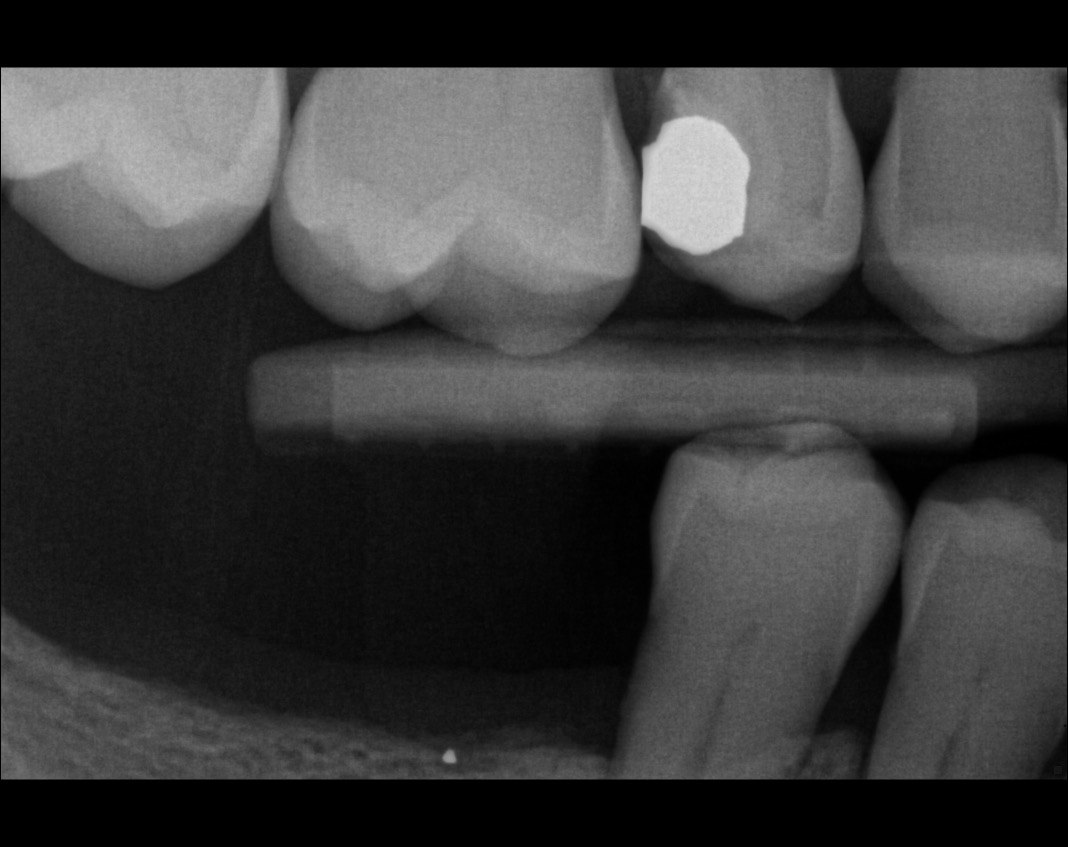

Question 26: What option cannot be selected for mesial tooth surface # 2.8?

Question 27: What options cannot be seen in this X ray?

Question 28: What is the best option that describe distal surface of tooth # 3.5?

Question 29: What options cannot be seen in this X ray?

Question 30: What options can be selected for the tooth # 4.2?

31. What option cannot be selected for the tooth # 3.6?

32. What options cannot be seen in the print of this X ray?

33. What options cannot be seen in the print of this X ray?

34. What option can be selected for tooth # 4.6?

35. What options cannot be selected for the tooth # 1.5?